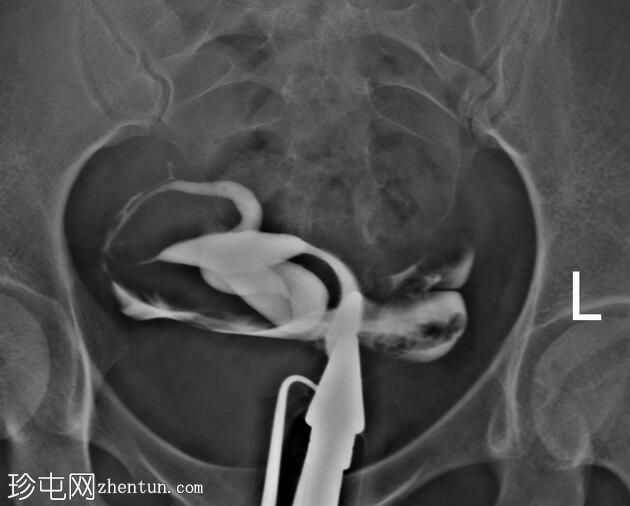

子宫体位于盆腔右侧旁中线,形态及轮廓正常。

宫颈管长度及黏膜表面正常,扩张正常。

右侧输卵管充盈,呈逐渐扩张,内有造影剂残留,无因输卵管积水导致的造影剂溢出。

左侧输卵管出现腹膜溢出。